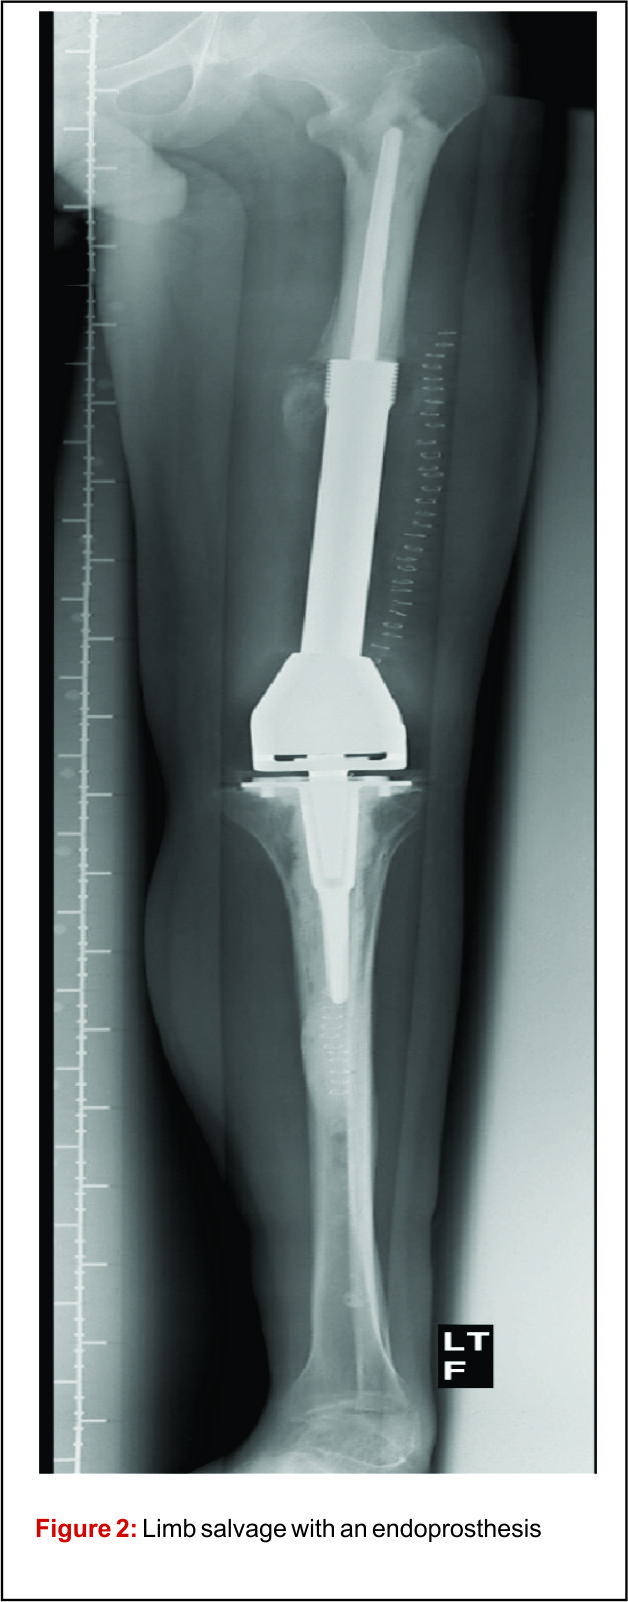

From www.orthobullets.com

Surgical margins and handling of softtissue in extremities a Canine Soft Tissue Sarcoma Surgical Margins Although local recurrence following surgical resection is the. Comparative lessons from human soft tissue sarcoma that may be important for the canine patient in the future include (1) understanding the. Comparative lessons from human soft tissue sarcoma that may be important for the canine patient in the future include (1) understanding the. Soft tissue sarcomas are derived from tissues of. Canine Soft Tissue Sarcoma Surgical Margins.